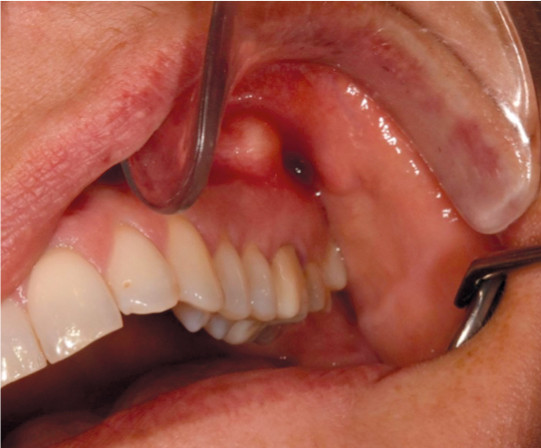

The condition is usually asymptomatic. However, the production of pus can result in the formation of a periapical abscess (Figure 1). This usually causes pain, swelling and occasionally fever. Periapical infections can also spread to surrounding structures (Figure 2). Draining of pus via a fistula (extra- or intraoral) will reduce symptoms. Acute periapical abscesses must be rapidly drained of pus, either via the root canal or via an incision. This procedure is primarily performed by dentists.

Figure 1 Periapical abscess from upper left molar.